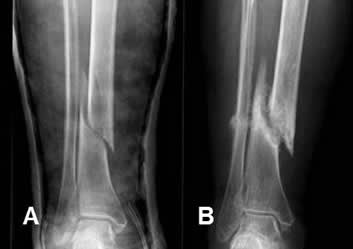

Fig 108. Consolidación retardada.

A: Rx AP. Fractura espiroidea en la tibia, que se manejó con reducción cerrada y estabilización con yeso.

B: Rx AP. En Rx control a los 4 meses, no hay formación de callo óseo. Los extremos no están en contacto y son escleróticos.